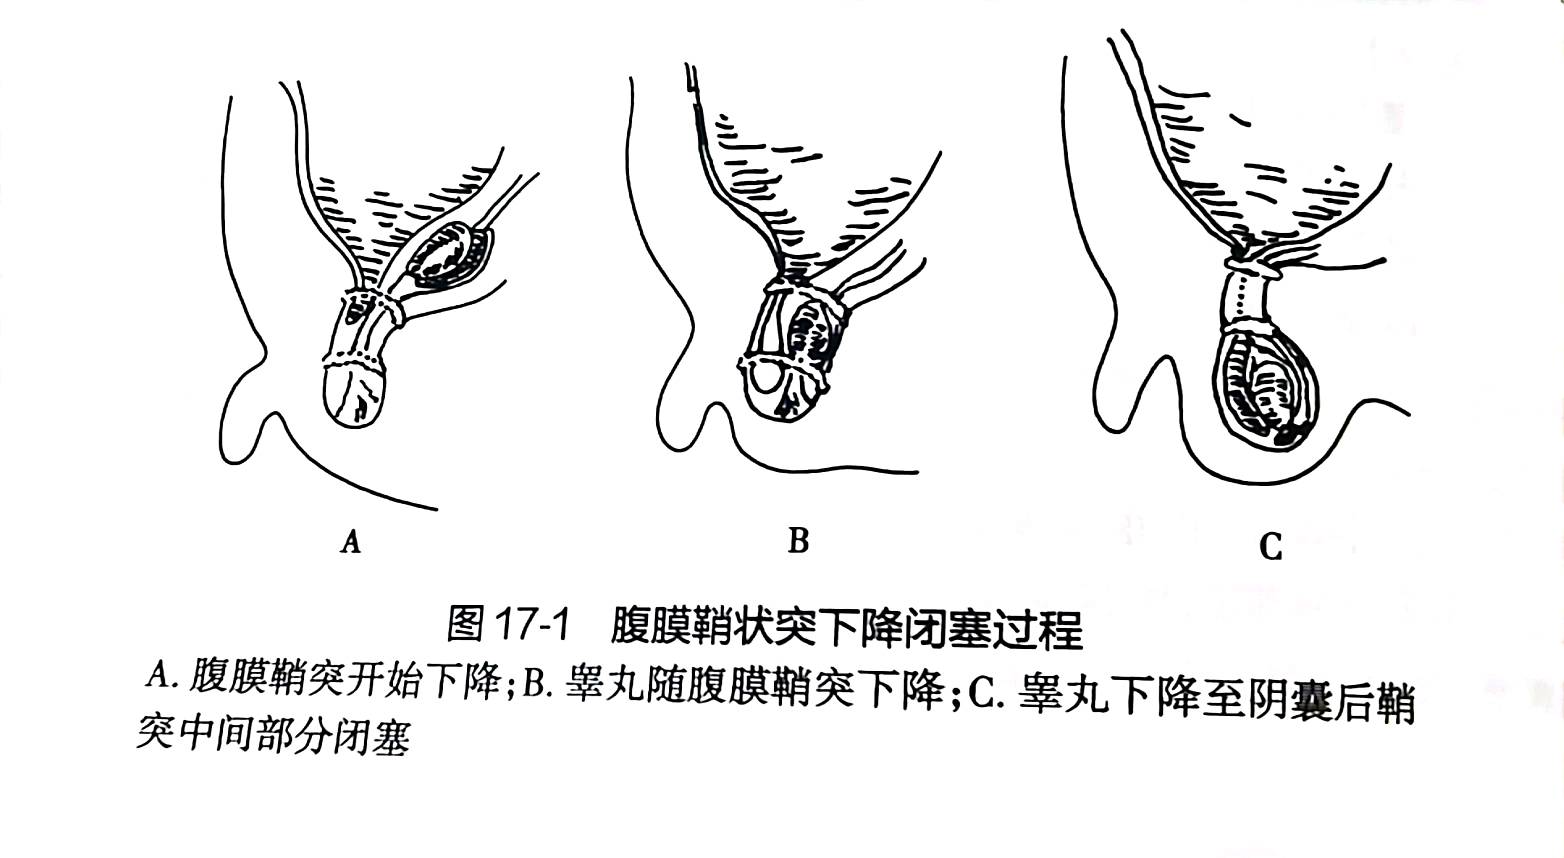

小儿腹股沟斜疝,是小儿外科最常见的疾病之一,患儿在出生后,腹膜鞘状突关闭发生停顿、延迟或不完全,使鞘突管仍然保持开放或部分开放,造成疝和积液发生的可能。其发生率约为0.8%-4.4%。常发生在1岁以内,男女发生率比例为3:1~10:1。

教科书上明确指出:因腹股沟斜疝容易嵌顿,腹股沟疝一经诊断后,应尽早进行手术治疗,以免发生嵌顿疝导致严重后果。手术治疗腹股沟疝已相当安全,可不受年龄限制。我科曾成功对出生7天宝宝的腹股沟斜疝进行腹腔镜手术(因腹股沟斜疝嵌顿)。腹腔镜下疝囊高位结扎术在我国技术成熟,其优点为术中精索损伤小、术后切口小,另外腹腔镜可以探查到对侧内环口未闭合时同时给予预防性结扎,传统开刀手术存在对侧再发需再次手术可能。